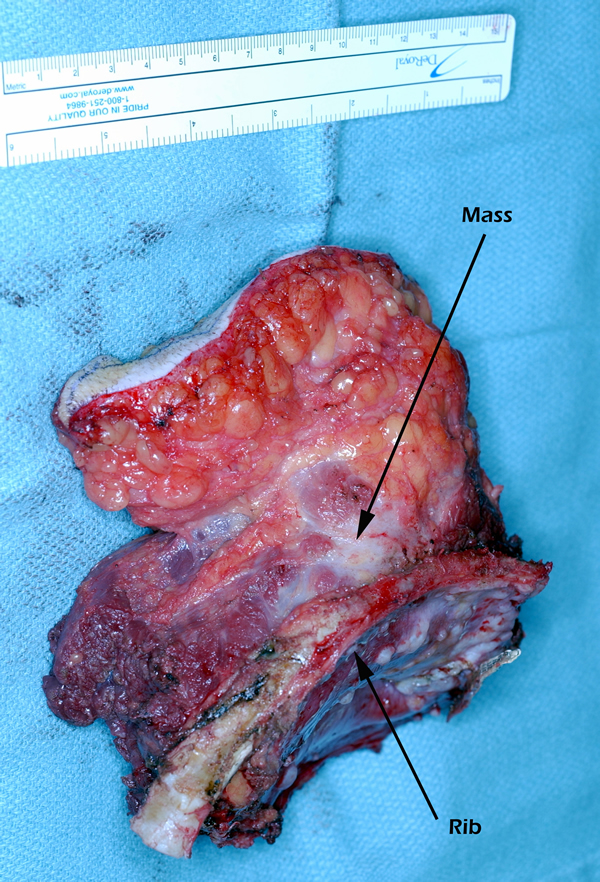

Eleven months later, he presented with a several month history of a painful fixed, firm mass over the pectoral area of the left chest and a smaller mass inferior to this (Figure 1). CT scan demonstrated a new 2 cm nodule in the left upper lobe associated with an anterior chest wall mass six centimeters in size in addition to bilateral new pulmonary nodules (Figure 2). The mass was tethered to the skin and in danger of eroding through it. The patient underwent en-bloc resection of the chest wall and adjacent lung (Figures 3a-c). The resulting defect (Figure 4a) was reconstructed with 2 mm Gore-Tex patch (Figure 4b) and pectoralis major muscle flap (Figure 4c) with primary skin closure (Figure 4d). The pathology revealed metastatic chordoma (Figures 5a-d). The patient recovered well, leaving the hospital on the sixth postoperative day.

The appropriate treatment for chest wall metastases for chordoma is not known due to the rarity of this occurrence. Indications for chest wall metastasectomy include resection for diagnosis, local control, and palliation / prevention of skin ulceration and rarely for cure or as part of a multidisciplinary approach [7]. While radiation therapy is another option for local control, its ability to prevent progression of disease is unpredictable and unknown in the case of chordoma. Once the area of the chest wall has been irradiated, subsequent resection and reconstruction is more difficult and prone to failure [8, 9]. In the presented case, resection was performed for local control, pain relief and to prevent the complications of ulceration, necrotizing infection and bleeding from a tumor eroding through the anterior chest wall. The principles of chest wall resection were adhered to by performing a full thickness en-bloc resection of the mass, reconstruction with a two mm Gore-Tex patch and coverage with a well-vascularized myocutaneous flap.